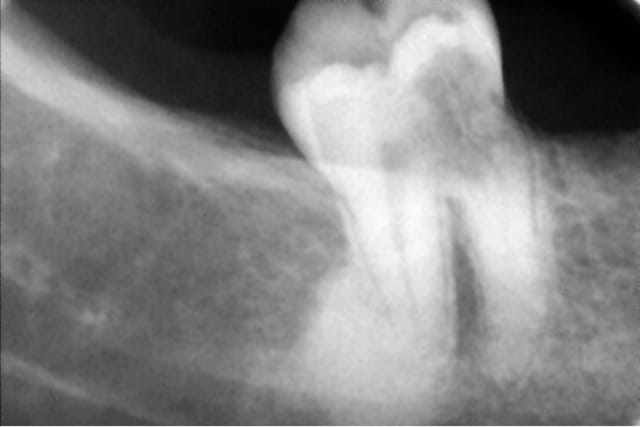

Une patiente se présente avec un abcès paro en vestibulaire de 47, elle prend des antibios depuis 5 jours. Pour le reste tout va bien et elle a une hygiène correcte.

Voilà les radios, dont une trouvée dans son dossier, qui date de 3-4 ans.

Sous la gencive, il y a un petit trou au collet de la dent, en vestibulaire. Mais la sonde s'enfonce et c'est douloureux.

IL y a une résorption peut être externe au niveau cervical mésial, et une pulpite chronique qui provoque une ostéite condensante apicale sur la racine distale. Ca fait beaucoup pour pouvoir conserver cette dent dans de bonnes conditions.

C'est la résorption qui est préoccupante : en général, ça détruit la dent en faisant de minuscules micro canaux sanguinolents. Impossible d'éradiquer ça.